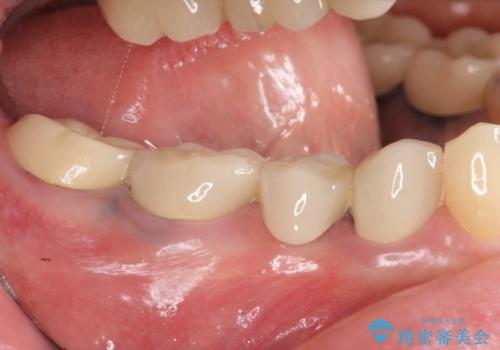

- 右下でものを咬むと痛むので診て欲しいといらっしゃった方の症例です。

右下6番目の歯を診査したところ歯根が破折していたため、保存不可能であることを説明し抜歯しました。

その後右下5、6番目にはインプラントを埋入し、右下3、4、5、6、7番の歯の補綴をオールセラミッククラウンによって行いました。

カスタムアバットメントは患者様それぞれの歯茎に合わせて製作されたオーダーメイドのアバットメントです。

既製のアバットメントに比べ適合がよく、高い清掃性を誇ります。